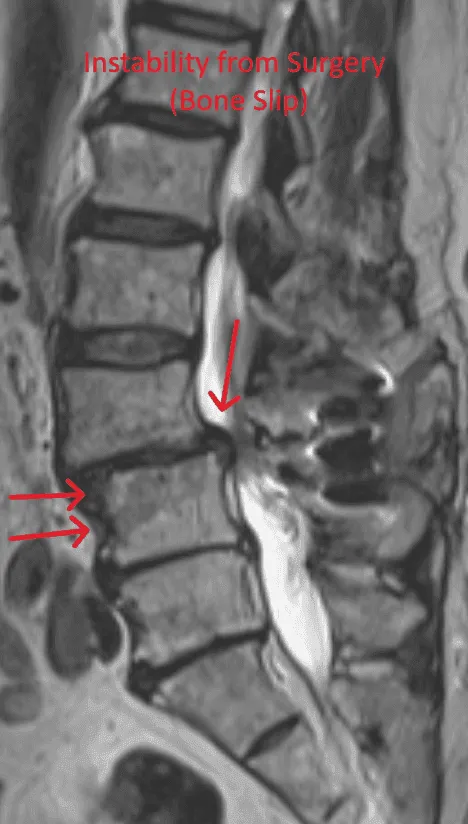

MRI of the spine showing bone slip due to post-surgical instability, indicated by red arrows.

Spinal Instability

Bone destruction from the procedure causes vertebral instability requiring fusion with screws and rods.